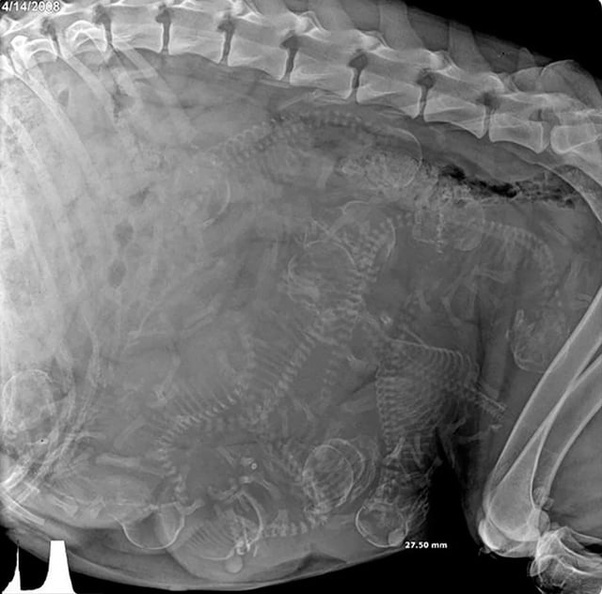

2. Рентген беременной собаки. Не знаете, сколько щенков будет?